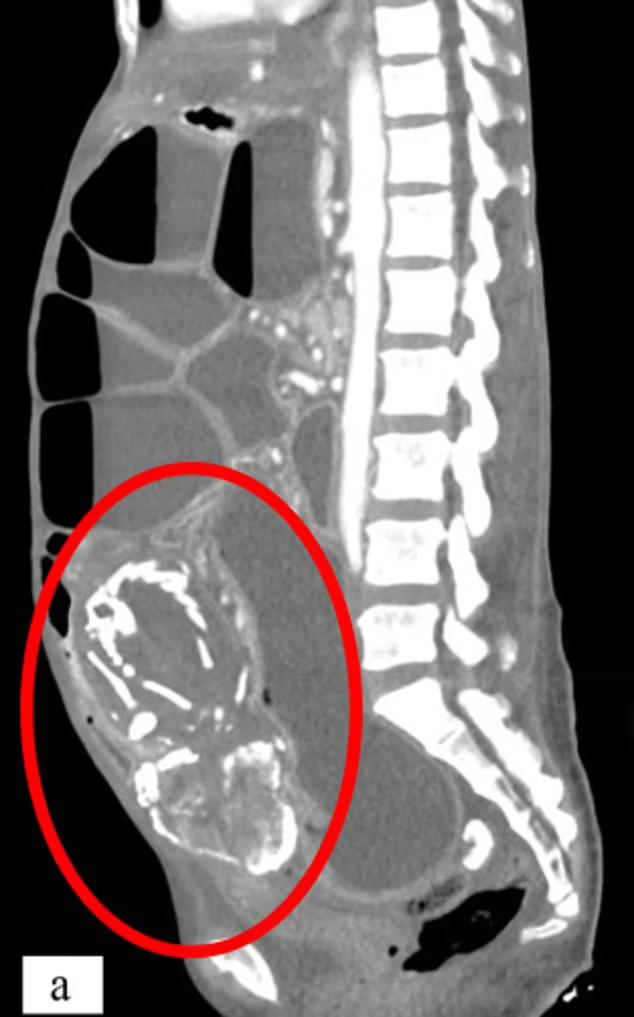

(这位难民女性的腹部扫描)

根据CT扫描的发现,她的腹中有一个长15-20厘米的石胎,能清晰看到胎儿的骨架。因为石胎体积较大,压迫了她的诸多脏器,导致了一系列健康问题。

第一个就是常年消化不良、腹痛。9年来,因为钙化的石胎压迫大小肠,她一吃多就吐,严重的时候吐胆汁,所以不敢多吃,导致营养不良,体质很弱。